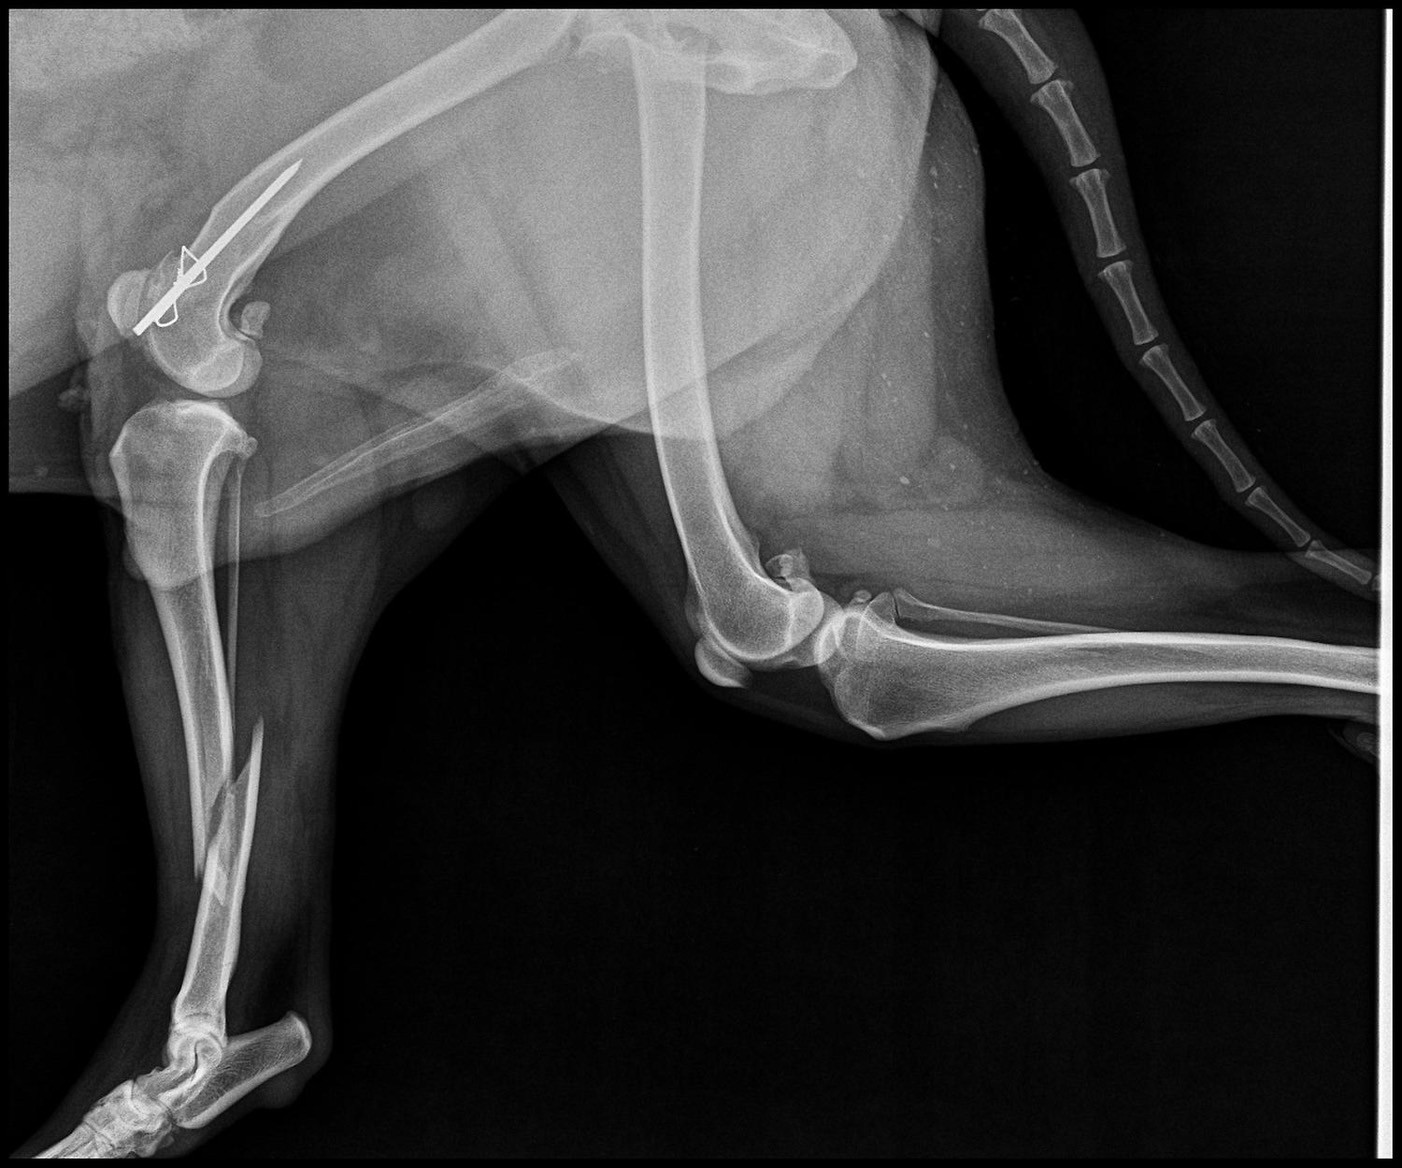

น้องปอม” สุนัขพันธุ์ไทยน้ำหนัก 27 กิโลกรัม ถูกนำตัวเข้ารับการตรวจรักษาที่โรงพยาบาลสัตว์ วิทยาลัยสัตวแพทยศาสตร์อัครราชกุมารี มหาวิทยาลัยวลัยลักษณ์ หลังประสบอุบัติเหตุถูกรถชน ทีมสัตวแพทย์ได้ทำการ เอกซเรย์ (X-ray) พบว่า กระดูกหน้าแข้งข้างขวา (right tibia) ของน้องปอม หักแบบเกลียวบริเวณกลางกระดูก (Spiral fracture at midshaft of right tibia) ซึ่งเป็นการแตกหักจากแรงบิดที่ทำให้กระดูกแตกเป็นแนวเกลียว